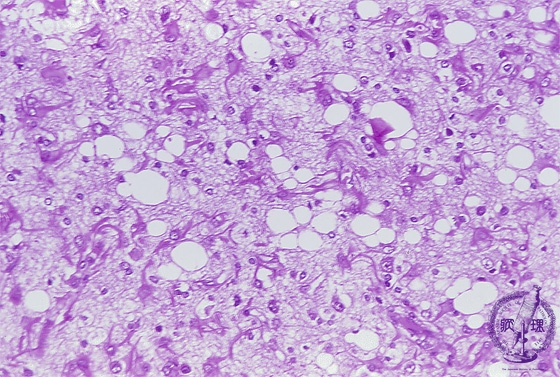

- (6)Creutfeldt-Jacob disease

Microscopic findings (H.E. high magnification) Various-sized vacuolation (spongiosis) was extensively detected in the cortex following loss of neurons, so that the disease was also termed as spongiform encephalopathy. Proliferation of glial cells is also apparent.